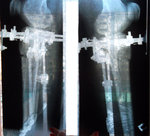

Это мои ножки. Сегодня 5 день. До сих пор не верю, что это происходит со мной. Как будто это сон. У меня двое маленьких детей, быт, куча дел, все не решалась, все думала как я их оставлю, как они без меня. Но все таки решилась! Ура! Я рада, что приближаюсь к своей мечте! Терпения, конечно, надо немалого, но мысль о ровных красивых ножках дает столько сил. Нас в данный момент двое, я и loginza499, у нее сегодня 18 день, исходники наши почти похожи, только ножки у нее худее. У нее уже заканчиваются Крутки и я вижу ее результат, ножки реально стали ровными. Я рада за нее и ее результат мне придает столько сил и уверенности. А в общем что касается больницы, персонала, то мне все нравится. Все вежливые, спокойные. Тут бессменная, незаменимая Маришка, молодец! Во всем поможет, позаботится. Кто лежал, знают.

Добрый день, Наталья.

Как ваши дела? У меня все отлично. Потихочнеку воостанавливаюсь. Одеваю юбки, платья и до сих пор не могу поверить что, это я и мои ножки!

Какое же это непередаваемое чувство, когда ты ходишь по магазинам и не проходишь как раньше мимо стеллажей с короткими юбками и платьями!

Вот прошло 1,5 месяца и как требуется сделала рентген, высылаю его. Передавайте Николаю Николаевичу большой привет и слова благодарности от меня!